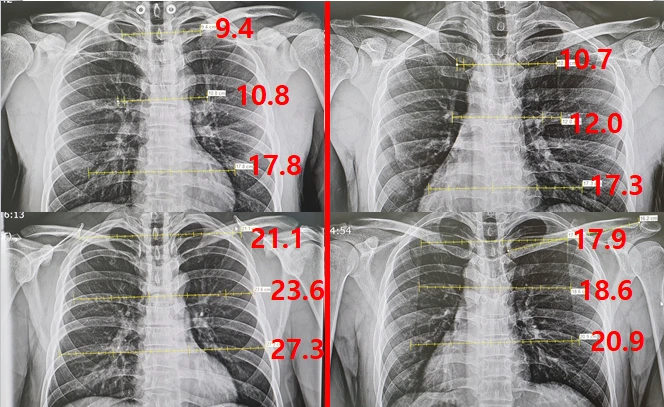

비교적 최근에 유튜브 Shorts 와 틱톡 에서 유행했던 어깨의 중요성 이라는 영상을 보신 분들이 있겠죠? 그에 착안하여 신쌤이 1. 견갑골을 완전히 후인하강 했을때, 2. 일상상태에서 힘을 빼고, 3. 견갑골을 뺀 "라인업" 상태 에서 X-ray 를 촬영하여 견갑골 사이의 거리를 측정해 보기로 했습니다.

견갑측정방법.PNG 흉부 X-ray 기준으로 견갑골 사이의 거리를 위,중간,아래 지점으로 나누어 측정하여 비교하였다.

측정 기준은 견갑골의 맨 위와 아래사이의 너비, 그리고 중간지점의 너비를 측정했는데, 견갑골의 특성상 위쪽을 축으로 아래부분이 바깥으로 회전하는 움직임을 그리기 때문에 한 곳만 측정하는 것 보단 이렇게 나눠서 측정하는 편이 더 좋은 결과를 얻을것이라고 생각했습니다.

x-ray.PNG 맨 위부터 1. 견갑골 후인하강 / 2. 일상상태에서 힘빼고 / 3. 광배를 뺀 "라인업" 포지션

견갑골을 후인하강 했을때는 평소상태와 비교했을때 상부부터 하부로 55.4%, 54.2%, 34.8% 견갑골 사이 너비가 감소(절반 이하로 감소)

했으며 반대로

견갑골을 밖으로 빼는 라인업 포지션을 했을 때는 6.2%, 14.8%, 14% 늘어나는 결과

를 보였습니다.

단순 수치를 보았을 때 키 174cm의 남자 헬스 중급자(신쌤 개인 의견) 기준으로 견갑을 완전히 후인하강 하면 견갑의 너비가 약 10cm정도 줄어들며, 반대로 견갑을 밖으로 빼면 평소상태보다 4cm정도 넓어 보이는 효과가 있다고 볼 수 있겠습니다. 물론 신쌤은 견갑을 빼는 포지션을 많이 연습하지 않으므로 이에 익숙한 사람이라면 더 넓은 기대값을 가질 수도 있겠다는 생각은 덤입니다.

재형 vs 원익.PNG 좌측이 웨이트 트레이닝한 신쌤의 후인하강과 평소상태, 우측이 의사1의 후인하강과 평소상태

상당히 흥미로운 결과가 나왔는데,

후인하강 한 상태에서는 오히려 운동을 하지 않은 의사1이 견갑골 사이의 거리가 미세하지만 더 넓게(0.5 - 1.3cm) 나왔지만,

평소 상태에서는 신쌤이 의사1에 비해 4-6.4cm 정도 더 넓게 측정

되었음을 확인할 수 있습니다.